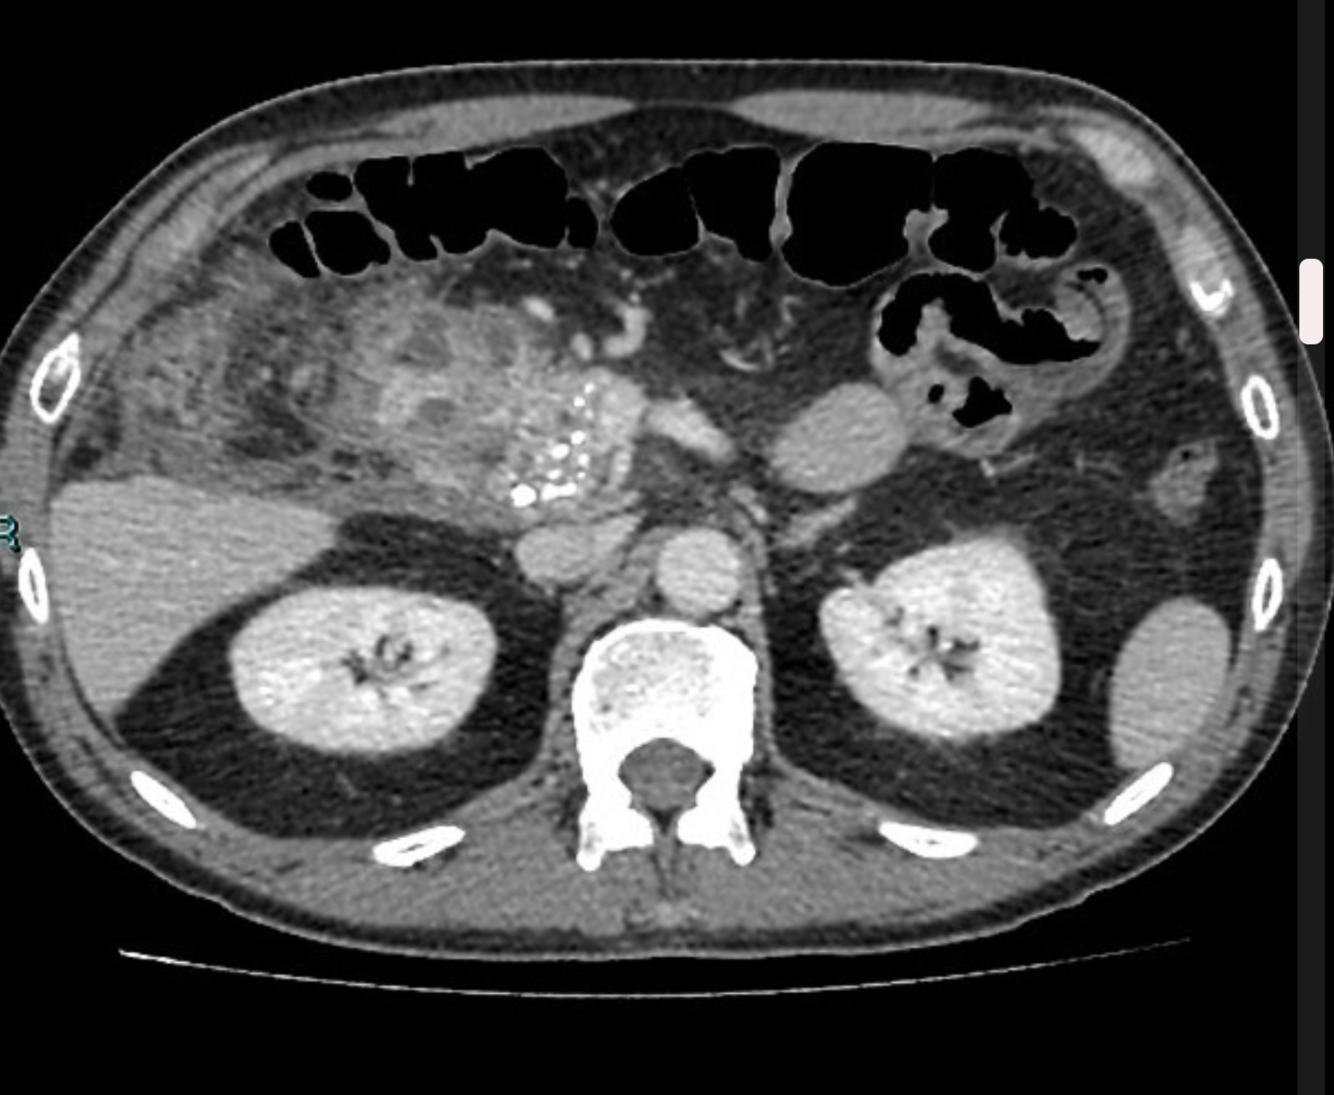

Complications of Chronic Pancreatitis

Generalised atrophy of body and tail of the pancreas. Diffuse parenchymal calcification with main pancreatic duct dilated throughout its course with a beaded appearance reaching up to 10mm in diameter. Multiple intraductal calculi are present, the largest measuring 10 mm in the pancreatic head. This stone is obstructing the main pancreatic duct resulting in ductal dilatation. No hypoenhancing pancreatic parenchymal lesions. No peripancreatic fat stranding or localised collections. No radio-opaque stones in the gallbladder, cystic duct, or common bile duct. No intrahepatic biliary duct dilatation.

Case Discussion

When presenting with an episode of abdominal pain, this patient underwent an ultrasound of the abdomen which revealed features of chronic calcific pancreatitis. However, due to the suboptimal acoustic window, a CT scan was recommended to rule out any pancreatic inflammation or neoplasm. The chronic inflammatory changes result in reduction in volume of pancreatic parenchyma with only a ghost of the gland remaining in the latter stages. These patients are more prone for neoplasms and have to be watched closely.